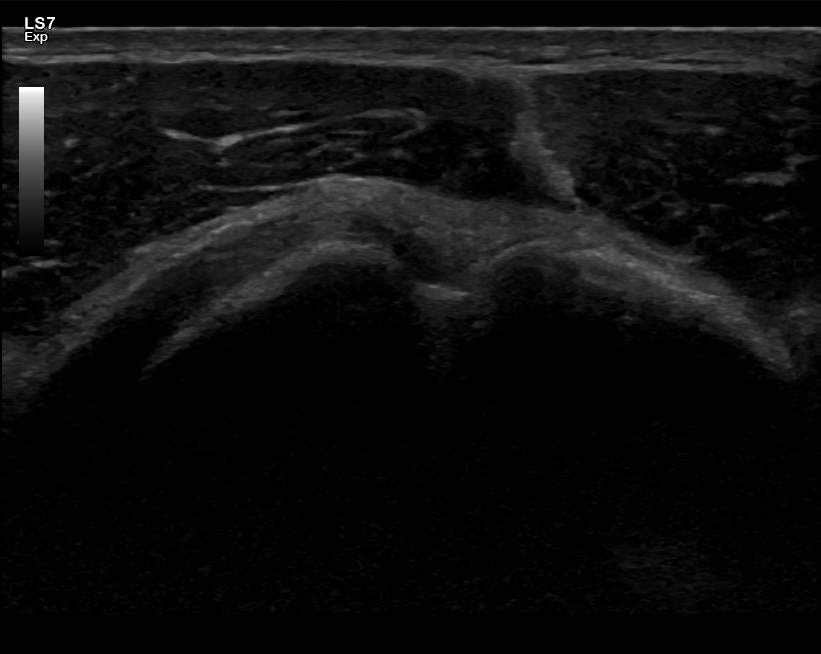

Olkapään ultraäänitutkimus

Olkapään ultraääni soveltuu erinomaisesti jänteiden ja kiertäjäkalvosimen rakenteiden arviointiin. Olkapään jännevammat ovat tavallisia ja voivat aiheuttaa kipua sekä liikkeessä että levossa. Tutkimukseen hakeudutaan useimmiten olkapään kivun ja liikerajoitusten takia.